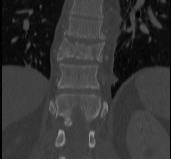

CT

Look for canal compromise

- cord signal change

- kyphotic deformity

Retropulsed fragments

- always between pedicles

- typically one or two main fragments (saloon door)

- assess canal compromise